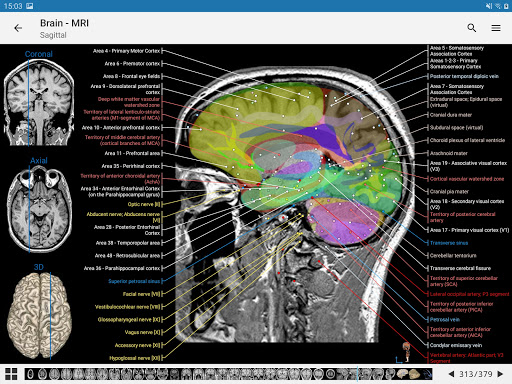

- وحدتان جديدتان: الدماغ - TOF والأوعية الدموية الدماغية ، أطلس التشريح الوعائي العصبي الطبيعي لشرايين الدماغ على الأوعية الدموية الدماغية. - تم إعادة صياغة الواجهة. - تتوفر علامة تبويب جديدة باسم "QuickLinks" ، ترسل وحدات في أقسام من جسم الإنسان وتسمح لك بالسفر السريع إلى الوحدات التي تبحث عنها. الخلل الصغيرة الثابتة.